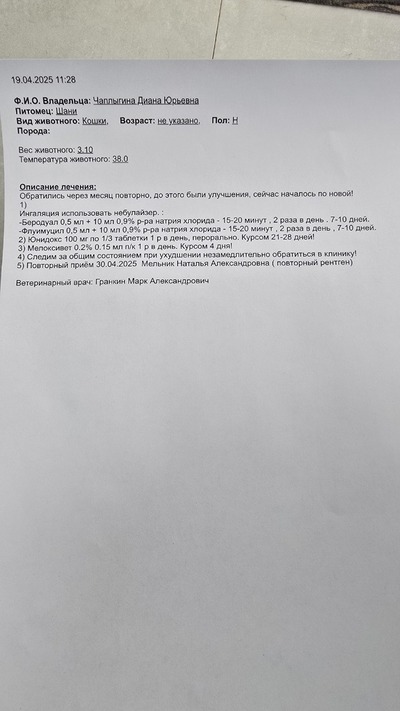

Кот, подобранец. После того, как был подобран, заметила хрипы и свист при дыхании.

Давала 8 дней амоксициллин. Свистов сейчас особо не слышу. Но есть странное дыхание у кота и раз -два в сутки кашель?.

Возможно есть тут знающие люди, что может быть с котом, чем можно лечить? Может ли такое состояние быть заразным для моих котов? Кот сейчас живет у меня на постоянной основе, даже на улицу не выходит, не хочет.

Температуры вроде нет, аппетит есть, может есть сутками напролет, если давать. Много пьет, и много писает, если это важно.